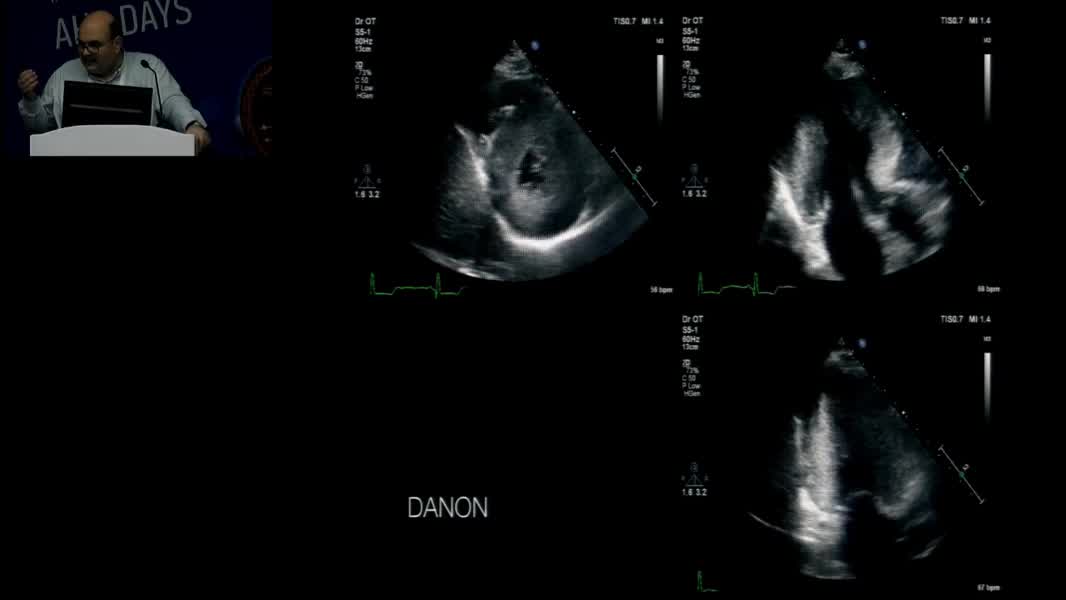

Echocardiographic Face Of Rare Cardiomyopathy And Fabry: Hands On Practical Echocardiography Course In The Diagnosis Of Fabry Disease And Cardiomyopathy Omaç Tüfekçioğlu (TR)

Nadir Miyokardiyopati ve Fabry’nin Ekokardiyografik Yüzü